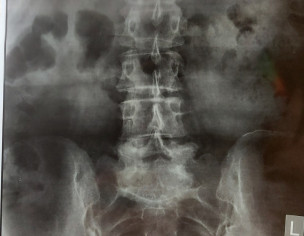

I have pain in my tail bone. Now I have when I sit or stand or lay on bed. Doc said its inflammation HISTORY--> tailbone was injured by falling 2 times at the same spot 5 years ago. I had that similar pain always while sitting or standing for long time but now it has increased n its very painful cant sit in my class. XRAY ATTACHED Thank you in advance